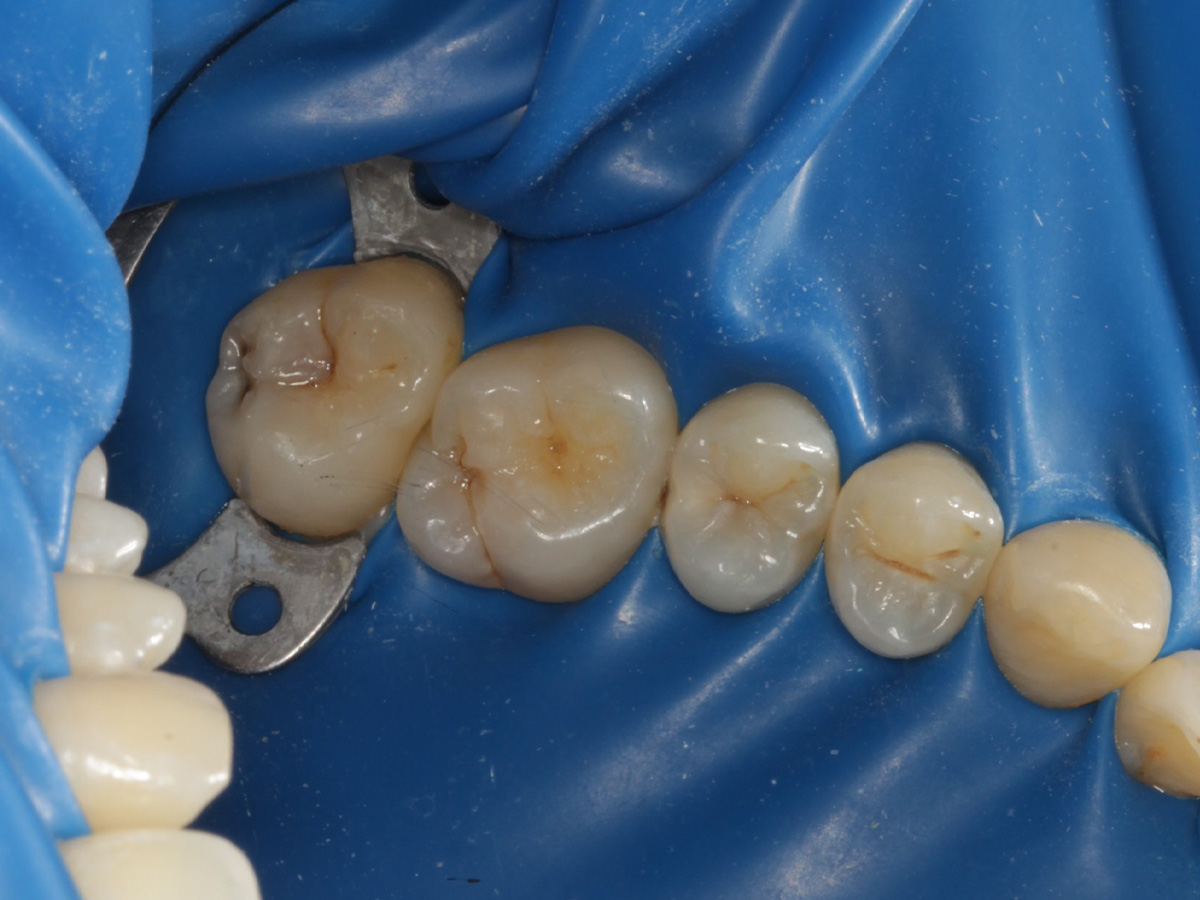

Abbildung 18

Fertige Restauration